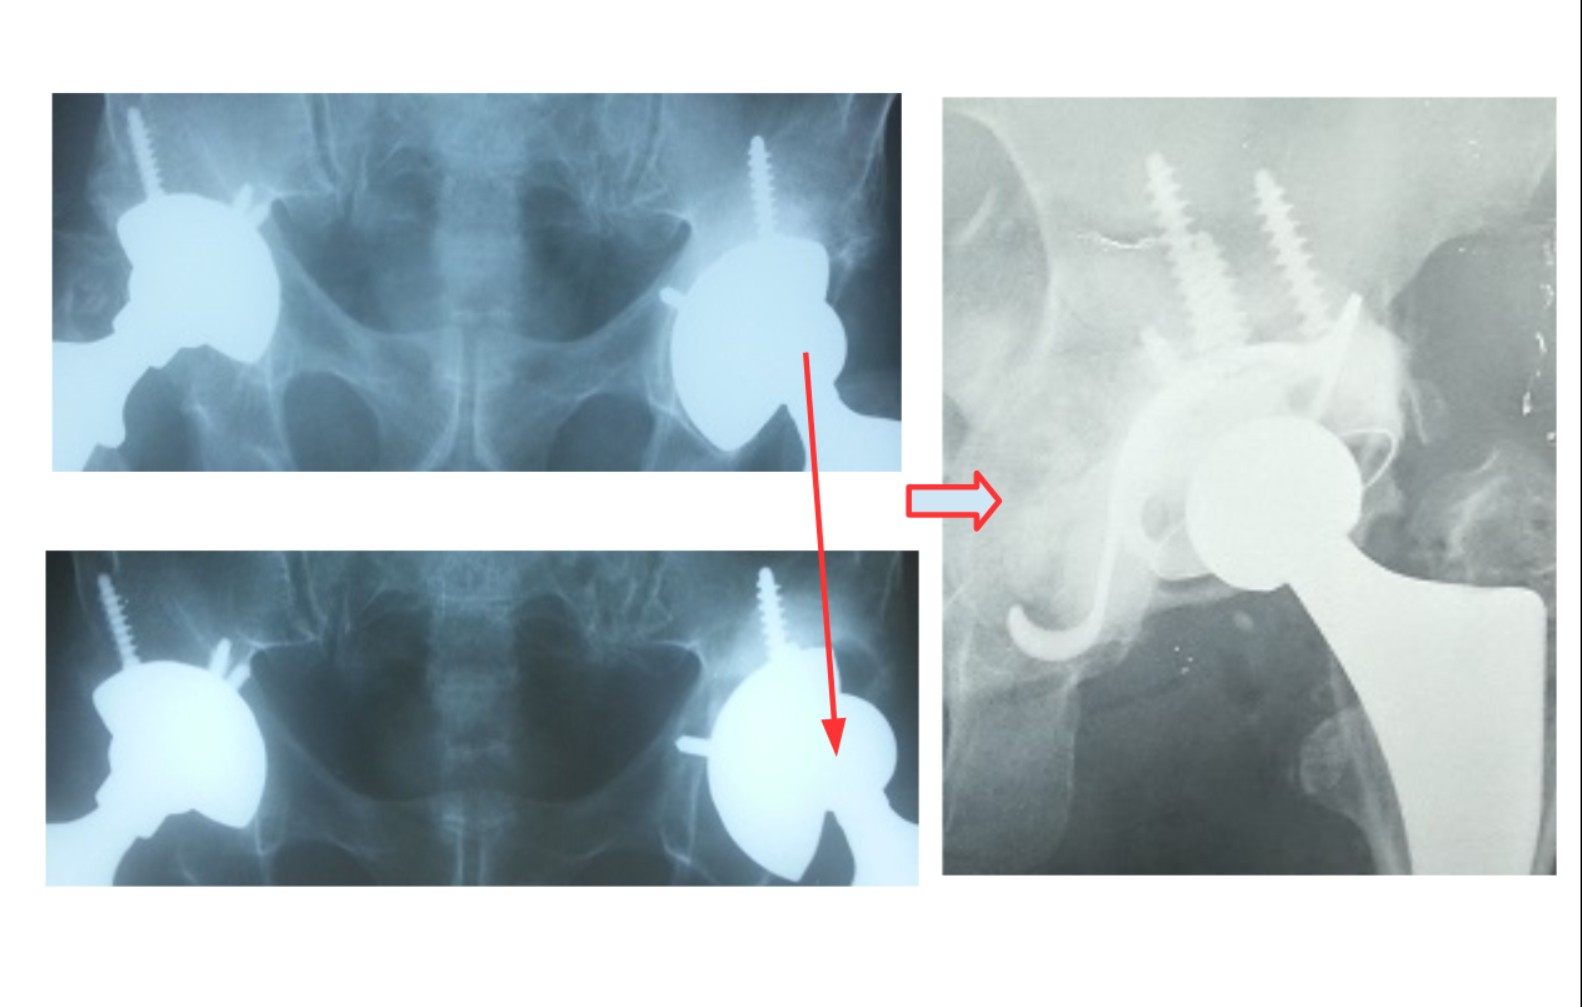

Στην εικόνα 4, κακή τεχνική οστικού τσιμέντου στη κοτύλη ΚΑΙ στο μηρό. Αποκόλληση ολόκληρης της κοτύλης, κάταγμα στο μηρό και εξάρθρημα, μόλις 2 μήνες μετά την επέμβαση. Αναθεώρηση με τοποθέτηση κοτύλης πορώδους τανταλίου και μακριά πρόθεση μηρού, με άριστο αποτέλεσμα, βάδιση χωρίς πόνο και χωρίς αστάθεια